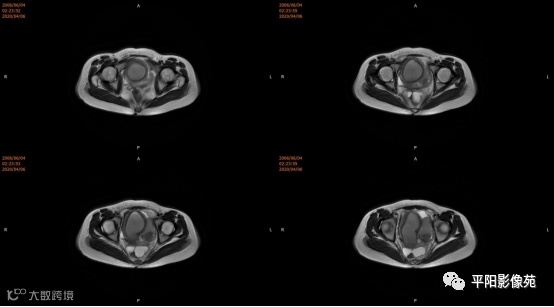

患者,女,13岁

主诉: 下腹部胀痛2+月,加重1天

现病史: 患者月经未来潮,2+月前无明显诱因感下腹部憋胀,间断胀痛,可忍耐,伴排便困难,自认为便秘引起腹胀,未在意。近1+月腹胀、胀痛次数增加,觉下腹部逐渐增大,小便正常。

您的诊断?

3.CT检查 对子宫、阴道的界限区分有一定限制,对子宫内膜、肌层难以分辨,故CT对子宫先天性异常的研究较少。阴道闭锁时,若宫腔内经血潴留,可见液性低密度聚集,子宫肌层密度均匀。

4.MRI检查 对软组织分辨率好,能够清晰区分子宫及阴道,对子宫内膜、结合带、肌层可清晰分辨;能明确子宫、宫颈、阴道结构异常的部位、范围、性质等。宫腔内经血潴留时,宫腔内见短T1长T2信号。